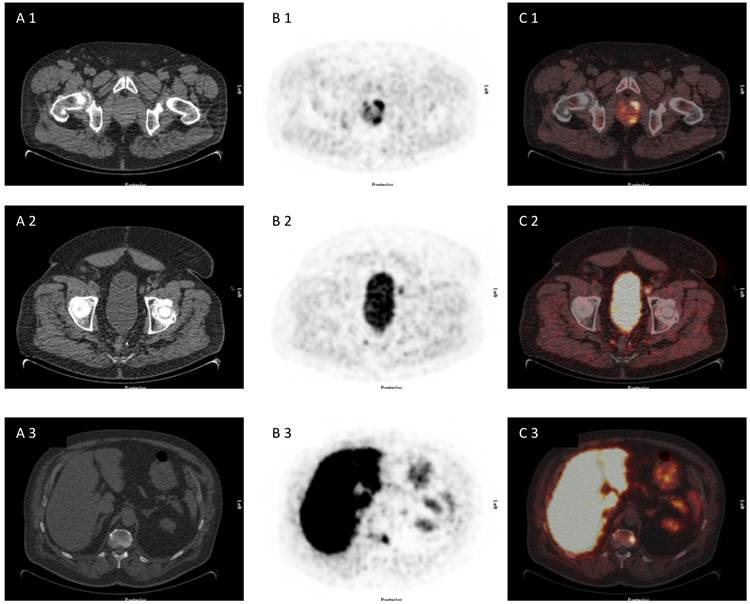

Fig 1

72 year old patient with biopsy proven prostate cancer, PSA 7,38 ng/ml, referred for [18F]FDG PET/CT for primary staging. [18F]FDG PET/CT revealed advanced disease of primary prostate cancer, iliacal lymph node metastases and bone metastasis (A 1-3) CT scan, (B 1-3) PET scan, (C 1-3) PET/CT fused images.